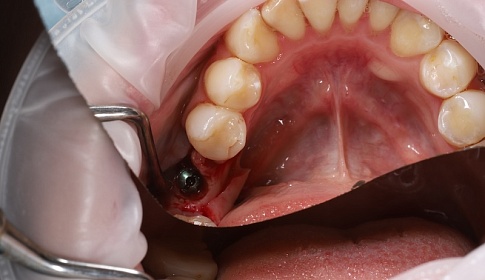

1 этап-хирургический:

- рассечение десны (готовится ложа для имплантата);

- устанавливается имплантат;

- ушиваются десневые ткани для изоляции имплантата.

Через 3 месяца после после полного приживления имплантата ткани десны повторно рассекают и устанавливают формирователь десны (готовится место для коронки).